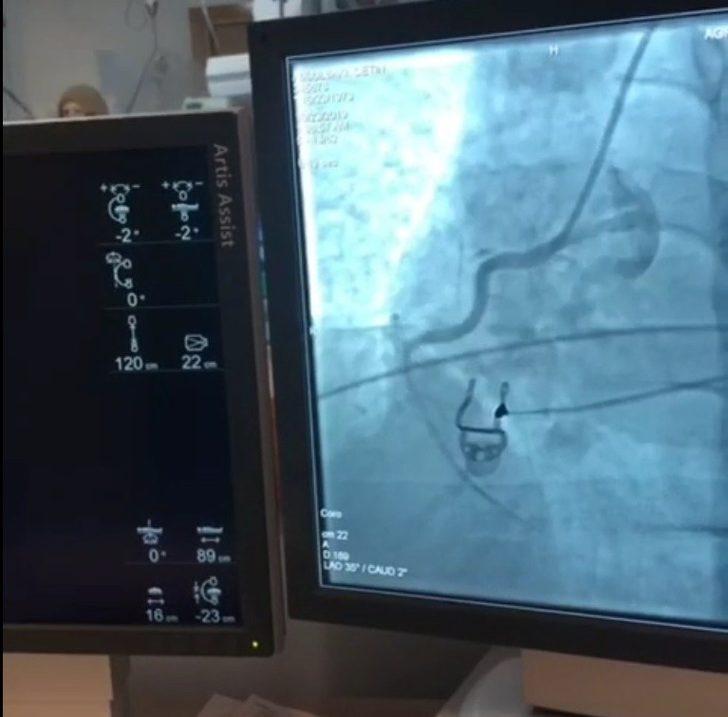

AK Parti Ağrı Milletvekili Ekrem Çelebi, Ağrı Devlet Hastanesi bünyesinde kurulumu tamamlanan 3’üncü Basamak Kardiyovasküler Cerrahi (KVC) Yoğun Bakım Ünitesi’nin tescilinin alındığını söyledi. Çelebi ayrıca, önceki gün faaliyete geçen Anjiyo Ünitesi’nde ilk anjiyonun başarılı bir şekilde yapıldığını kaydetti.

Milletvekili Ekrem Çelebi, önceki gün faaliyete geçen ve 15 Kasım’da tam kapasiteyle çalışmaya devam edecek olan Ağrı Devlet Hastanesi Anjiyo Ünitesi’nin ilk operasyonunu gerçekleştirdiğini belirtti. İlk anjiyografi işlemini başarılı ile tamamlayan Ağrı Devlet Hastanesi Başhekimi Coşkun Daharlı ve ekibine teşekkür eden Çelebi, “Anjiyonun ilimize kazandırılmasını sağlayan Cumhurbaşkanımız Recep Tayyip Erdoğan, Sağlık Bakanımız Farhettin Koca ve İstanbul Dr. Siyami Ersek Göğüs Kalp ve Damar Cerrahisi Eğitim Araştırma Hastanesi Başhekimi hemşehrimiz Prof. Dr. Cevdet Uğur Koçoğulları’na şükranlarımızı sunuyorum. Memleketimize hayırlı ve uğurlu olmasını diliyorum” diye konuştu.